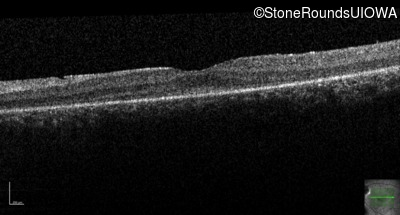

Age at visit: 15 years

This 15 year old male has had very poor vision and nystagmus since the first year of life.

Age at visit: 17 years